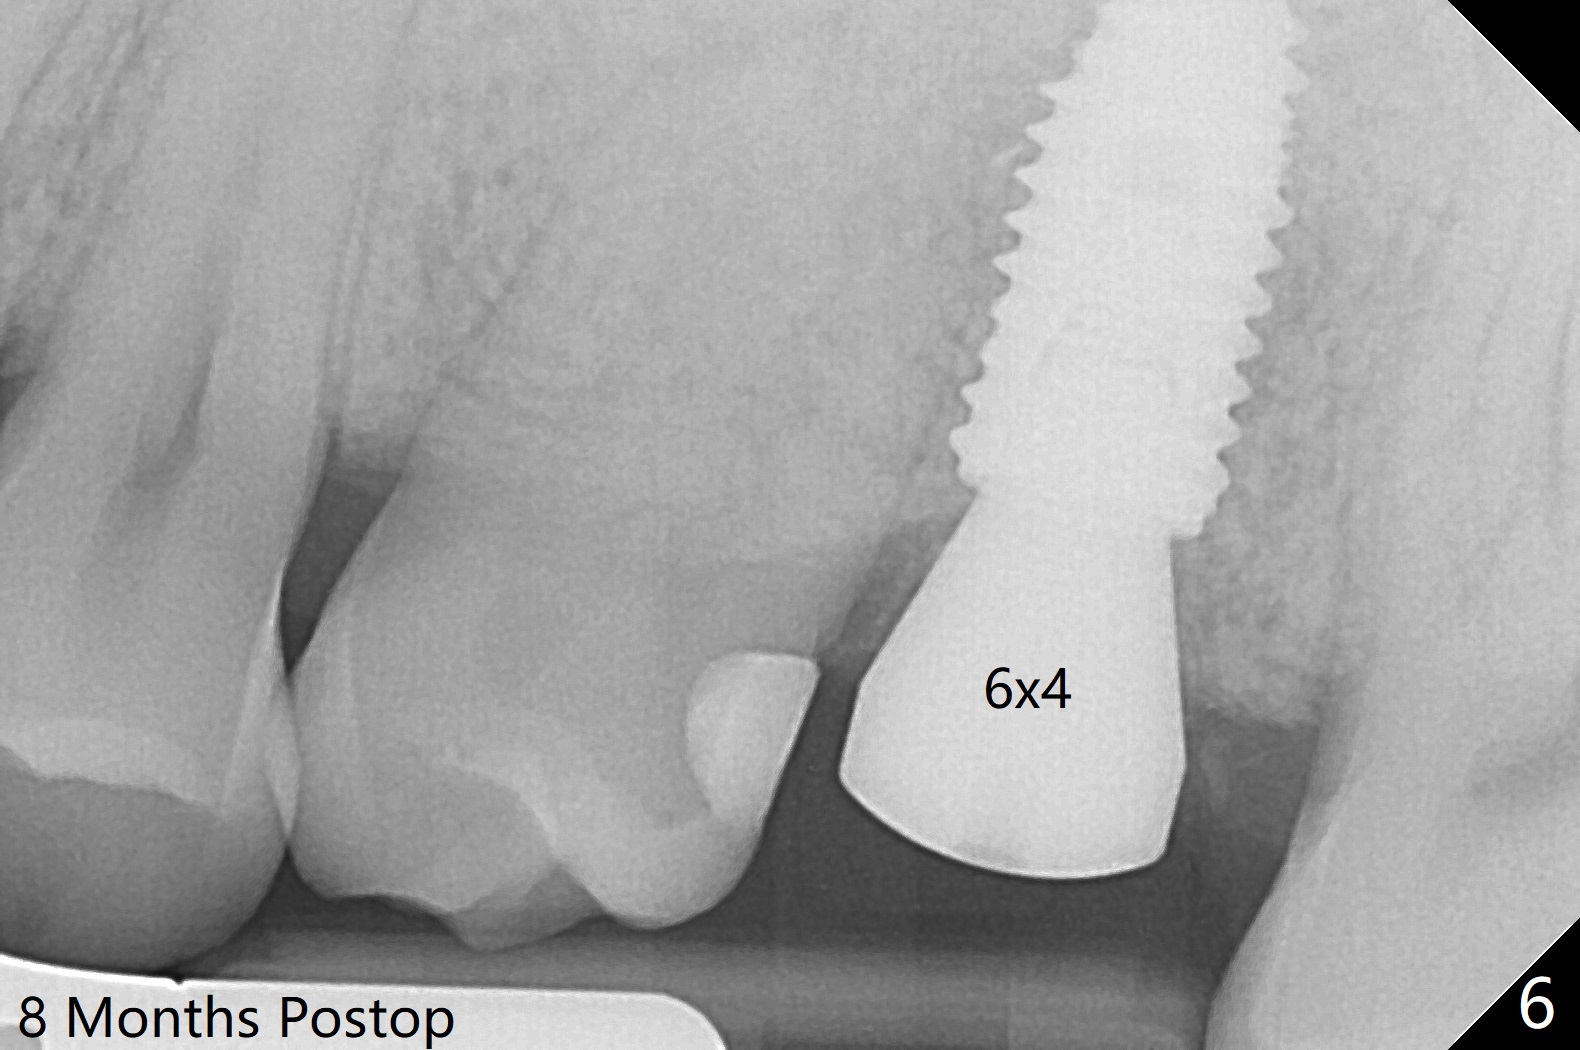

Low bone density is confirmed during osteotomy at #14 (6 months post socket preservation).  Underprep is adopted: after use of 3.5x10 mm drill instead of 4.5x10 mm one, a 4x10 and 4.5x10 mm dummy implant are placed for bone condensation.  When a 5x10 mm definitive implant is placed, it is unable to be placed to the depth.  After use of 4.0x10 mm, the final implant reaches depth ~ 1 mm more than planned.  But there appears no bone palatal to the implant clinically.  Small-field CT is taken.  In fact there is crestal bone palatal to the implant, but in small amount and in low bone density (Fig.1,2).  The implant should have been designed to be placed more buccal (Fig.3 arrow).  The implant also looks to be placed too close the root of the tooth #13, probably related to the rotation of #13 (Fig.4).  Unfortunately the patient does not agree to have limited orthodontics.  After palatal bone graft, GEM Cap is used to close the access with periodontal glue (Fig.5).  Spacer/periodontal dressing should have been used.  The wound heals 8 months postop, but 2-3 palatal threads are exposed with uncover.  After 6 mm profile drill and placement of a 6x4 mm healing abutment, allograft is placed palatal (Fig.6).  Upper Molar Immediate Implant, Trajectory II Shield Next Case of Buccal Defect  SP Xin Wei, DDS, PhD, MS 1st edition 11/19/2019, last revision 09/19/2020